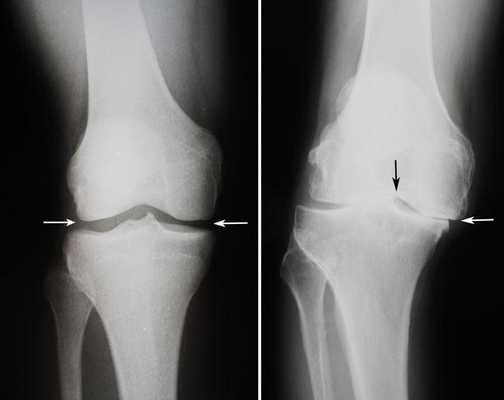

а) Предоперационное рентгенологическое обследование пациента включает рентгенографию конечности целиком на длинной кассете, рентгенографию стоя в переднезадней проекции, стоя в задне-передней проекции при сгибании коленного сустава, в боковой проекции и проекции Merchant (рис. 3).

Динамика болезни на рентгене.

Артроз коленного сустава на рентгене.

Показания к замене

Посмотрите на рентген, на нем вы видите, до какой степени при запущенном гонартрозе изношен гиалиновый хрящ, обеспечивающий гладкое скольжение суставных поверхностей. Концевые участки костей грубо деформируются нарушая функции сгибания и разгибания конечности вызывая интенсивный болевой синдром.